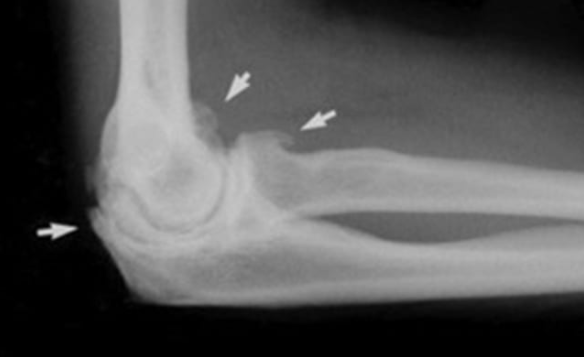

골절:Fractures

설명: 골절은 팔꿈치를 구성하는 뼈 중 하나 이상이 부러지는 것을 의미합니다. 이러한 부상은 주로 낙상이나 직접적인 충격으로 인해 발생합니다.

증상: 극심한 통증, 부종, 변형된 팔꿈치의 모양, 그리고 사용할 수 없는 팔의 기능입니다.

- X-ray (X선): 뼈의 상태를 평가하여 골절이나 관절염 같은 문제를 진단할 수 있습니다.